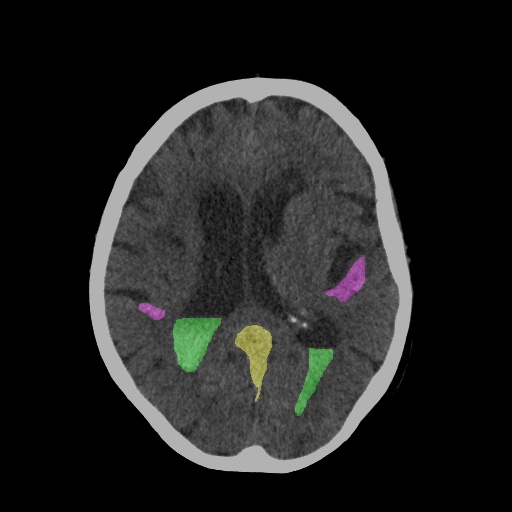

Cerebral Insight

HemoDetect: An AI based Assistant for Diagnosis of Brain Hemorrhage.